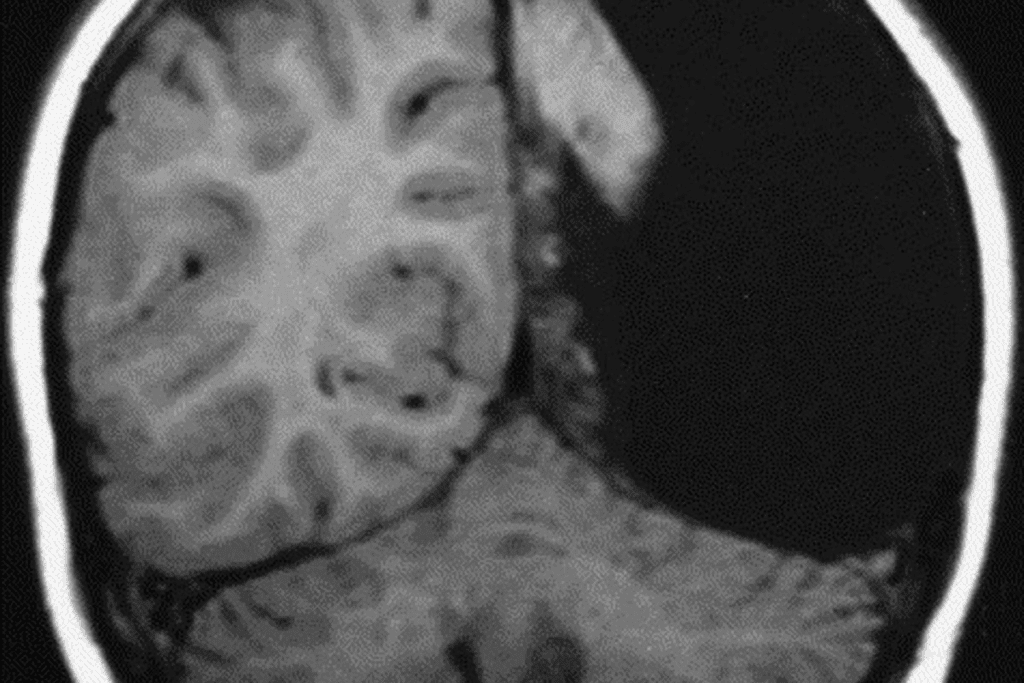

Neuroimaging Techniques

Neuroimaging is vital for finding brain metastases. We use MRI and CT scans to see the brain and find tumors.

MRI is great because it shows soft tissues clearly. It helps us see how big and where the tumors are. CT scans are quicker and easier to get, making them good for first checks and urgent cases.

| MRI | High-resolution imaging of brain structures | Detailed assessment of metastasis number, size, and location |

| CT Scan | Quick and widely available imaging | Initial assessment and emergency situations |